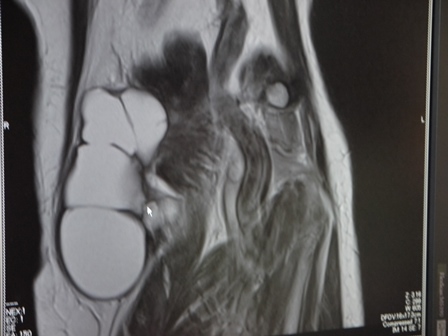

肘頭滑液包炎(ちゅうとうかつえきほうえん)は、 肘頭の先端の腫れ、発赤、痛みを特徴とする状態のことである。根本的な原因が感染によるものである場合は、発熱を生じる可能性がある。状態は比較的一般的であり、滑液包炎の一種であり最も頻繁にみられる種類である。

通常、肘への圧力や外傷、感染症、関節リウマチや痛風などの特定の病状などの結果として発症する。肘頭滑液包炎は、配管、鉱業、園芸、整備工などの特定の職種に関連している。根本的な機序は、肘頭と皮膚の間の液体で満たされた滑巻胞の炎症によるものである。診断は通常、症状に基づく。